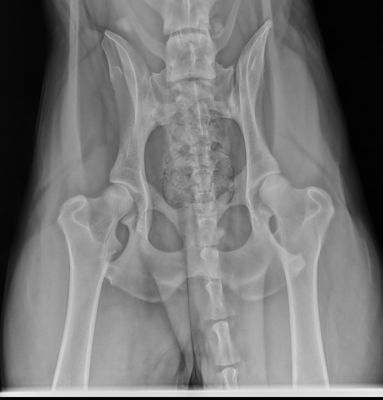

I'm no hip expert, by any means but I'd say Good or if nothing better, at LEAST a Fair from OFA.

The positioning needs to be symetrical, the legs parallel and the knees on the film and rotated inwardly. Exposure isn't great, but it's acceptable I think. I don't see any permanent left or right markings or any information on the dog or the owner. OFA rquires all of that.

Now, I know it isn't fair to discuss them because of the X-ray quality faults, but even so, the hips do not look alike to me, so that would suggest some issues? Like DDRCzechfan says, just trying to learn....

I too, Beetree thought the sockets looked a HAIR different, but as you said, it wasn't fair to comment being as they aren't OFA quality. Nothing against you, Mirasmom, to be honest, I'd probably have walked out the door of the vet's office not knowing any better and would've submitted them to OFA without a second thought.

I still think they look like Good hips though, and would hope they would continue to look good with a new xray of them